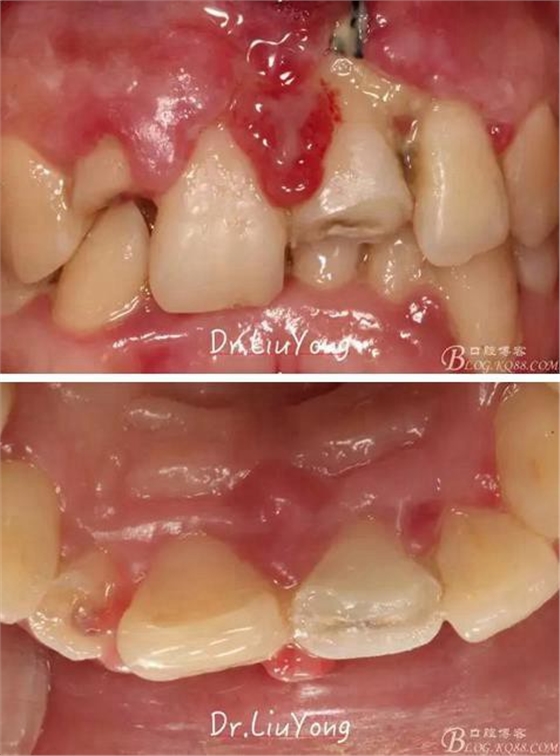

一、病例資料:

患者女性,39歲

主訴:上前牙外傷一月

病史:患者一月前騎車時不慎摔倒,致上下唇粘膜挫裂傷,上前牙牙齦挫裂傷,同時上前牙因外傷折斷,其余前牙松動明顯,受傷后在當(dāng)?shù)剡M(jìn)行清創(chuàng)縫合,外傷牙齒未予處理,現(xiàn)患者上下唇挫裂傷已愈合,因上前牙外傷來院就診。全身情況良好,無系統(tǒng)病史,無長期服藥史,無不良嗜好。

檢查:面部對稱無腫脹畸形,張口度正常,口內(nèi)檢查可見A2牙冠缺失,可見直徑約1.5mm左右穿髓孔,冷熱刺激痛+,叩痛+,探痛+,近中斷面探診位于齦下1.5mm,A1B1B2松動2-3度,B1牙冠缺失1/2,冷熱刺激痛-,叩痛+,B2牙冠完整,A2-B2牙齦紅腫,探診極易出血,全口口腔衛(wèi)生差,牙結(jié)石++,A1B1之間牙齦乳頭紅腫嚴(yán)重,B1唇側(cè)牙齦萎縮明顯,牙齦邊緣可見縫線兩處,局部有滲出,齦緣冠方1mm處見白色骨塊,松動,觸痛明顯,觸及骨塊時可見B1及B2近中唇側(cè)牙齦動度,B1B2之間唇側(cè)牙齦乳頭缺失,B2近中根面可見大量牙結(jié)石。重度深覆合,牙尖交錯位時C3-D2咬至上前牙腭側(cè)齦緣,A1切端咬至C12唇側(cè)齦緣。其余牙齒未見明顯異常。

診斷:

B1唇側(cè)牙槽骨折裂

A1-B2外傷后松動

A2冠根折

B1冠折

術(shù)前口內(nèi)照片如下: